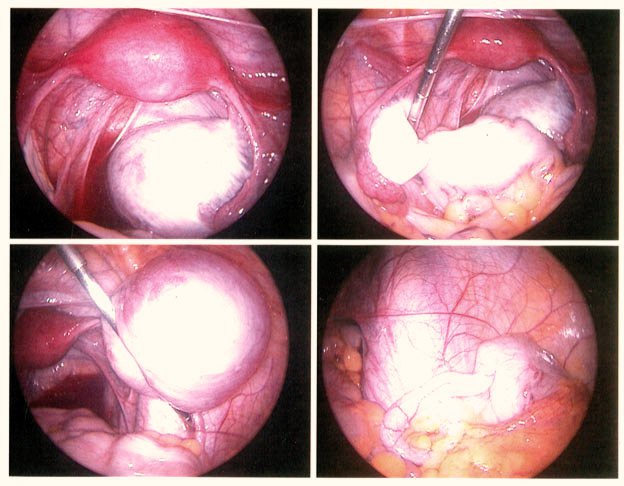

اندومتریوز معمولا با لاپاراسکوپی تایید می شود. این یک عمل کوچک است که شامل ایجاد یک برش کوچک، تحت بیهوشی، در دیواره شکم (شکم) زیر دکمه شکم (ناف) است. یک ابزار نازک تلسکوپ مانند (لاپاروسکوپ) از طریق پوست فشار داده می شود تا به داخل آن نگاه کند. تکه های اندومتریوز توسط پزشک قابل مشاهده است.با این حال، علائم آندومتریوز می تواند ناشی از شرایط دیگر باشد. بنابراین، اگر هر یک از علائم آندومتریوز بالا ماندگار شد، معمولاً آزمایشاتی برای یافتن علت علائم توصیه می شود.

لاپاراسکوپی

این روش جراحی با بیهوشی عمومی انجام میشود. پزشک از طریق یک برش کوچک در شکم دوربین کوچکی را وارد میکند تا به طور مستقیم داخل لگن را مشاهده کرده و در صورت نیاز نمونهبرداری (بیوپسی) انجام دهد. لاپاراسکوپی دقیقترین روش برای تشخیص قطعی اندومتریوز است و به پزشک این امکان را میدهد که ضایعات اندومتریوز را شناسایی و درمان کند.

در برخی موارد، پزشک متخصص برای بررسی دقیقتر، بیمار را برای انجام عمل لاپاراسکوپی به جراح ارجاع میدهد. لاپاراسکوپی نوعی جراحی کمتهاجمی است که با بیهوشی عمومی انجام میشود. طی این روش، برشی کوچک در نزدیکی ناف ایجاد شده و ابزاری باریک و بلند با دوربین کوچکی به نام لاپاراسکوپ وارد حفره شکمی میشود. پزشک از طریق این دوربین میتواند داخل شکم را مشاهده کرده و نشانههای وجود بافتهای اندومتریوز را بررسی کند. همچنین امکان برداشت نمونههای بافتی برای آزمایشهای بیشتر فراهم میشود. اطلاعاتی مانند محل دقیق، میزان گسترش و اندازه ضایعات با این روش بهدست میآید.

گاهی اوقات جراحی برای برداشتن برخی از تکه های بزرگتر اندومتریوز توصیه می شود. اگر مشکل ناباروری باشد، عمل ممکن است علائم را کاهش دهد و احتمال بارداری را افزایش دهد.تکنیک های مختلفی وجود دارد که می توان از آنها استفاده کرد. معمولاً یک ابزار نازک تلسکوپ مانند (لاپاروسکوپ) از طریق یک بریدگی کوچک در شکم (شکم) رانده می شود. سپس جراح از لاپاراسکوپ برای دیدن داخل شکم و برداشتن کیست ها یا سایر بافت های اندومتریوز (جراحی سوراخ کلید) استفاده می کند.

لاپاراسکوپی برای تشخیص و درمان آندومتریوزلاپاراسکوپی تحت بیهوشی عمومی انجام می شود. ممکن است یکی برای تایید تشخیص آندومتریوز داشته باشید. متخصص شما همچنین ممکن است در همان زمان رضایت شما را برای درمان هر تکه بزرگی که ممکن است پیدا کند (همانطور که قبلا توضیح داده شد) "در حالی که آنها در آنجا هستند" درخواست کند. این باعث صرفه جویی در انجام دو لاپاراسکوپی - یکی برای تشخیص و دیگری برای درمان می شود.

نحوه تشخیص آندومتریوز

لاپاراسکوپی

بیشتر آندومتریوز باید با دیدن آن به طور دقیق و مستقیم تشخیص داده شود. این بدان معناست که بیماران باید حداقل یک نوع جراحی جزئی به نام لاپاراسکوپی انجام دهند.

در این عمل یک برش کوچک در ناف ایجاد می شود و سپس یک تلسکوپ به داخل حفره شکم وارد می شود تا تمام اندام ها و سطوح لگن را به دقت بررسی کند. به این ترتیب می توان اندومتریوز را به درستی شناسایی کرد و شدت آن را ارزیابی کرد.

لاپاراسکوپی

این یک روش جراحی برای درمان آندومتریوز است که در آن جراح با استفاده از یک گاز بی ضرر، شکم را کمی باد می کند و یک ابزار بینایی کوچک را به داخل شکم وارد می کند که به آن لاپاراسکوپ می گویند. سپس جراح حداقل دو برش کوچک دیگر در شکم ایجاد می کند و لیزر را برای برداشتن ضایعات از طریق فرآیندی به نام بریدن وارد می کند. ضایعات با استفاده از گرمای شدید از بین می روند و رگ های خونی بدون بخیه بسته می شوند، با فرآیندی به نام کوتریزاسیون. گاهی اوقات جراحان بافتهای اسکار را نیز برمیدارند زیرا ممکن است بر درد آندومتریوز بیفزایند.